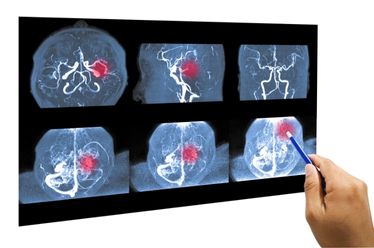

O Desafio do Diagnóstico por Imagem

A suspeita clínica deve ser investigada imediatamente com exames de imagem avançados. A Ressonância Magnética (RM) do crânio é o exame de escolha, pois fornece imagens detalhadas das estruturas cerebrais, permitindo identificar a localização exata, o tamanho e as características do tumor. Em alguns casos, a biópsia pode ser necessária para determinar o tipo exato de célula tumoral e guiar o tratamento.